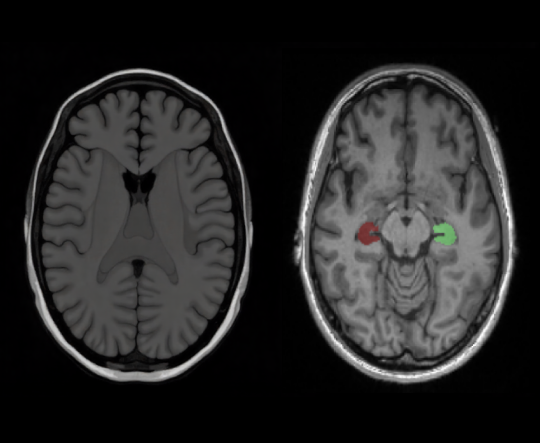

Alzevita is a cloud-based, AI-powered medical image processing software as a medical device intended to assist neurologists, radiologists and researchers with expertise in the analysis of 3D brain MRI scans. The software performs fully automated segmentation and volumetric quantification of the hippocampus, a brain structure involved in memory and commonly affected by neurodegenerative conditions.

Alzevita is designed to replace manual hippocampal segmentation workflows with a fast, reproducible, and standardized process. It provides quantitative measurements of hippocampal volume, enabling consistent outputs that can assist healthcare professionals in evaluating structural brain changes. The software supports image interpretation of MRI scans in both clinical and research setting.

The software performs fully automated segmentation and volumetric quantification of the hippocampus, a brain structure involved in memory and commonly affected by neurodegenerative conditions.

It provides quantitative measurements of hippocampal volume, enabling consistent outputs that can assist healthcare professionals in evaluating structural brain changes.